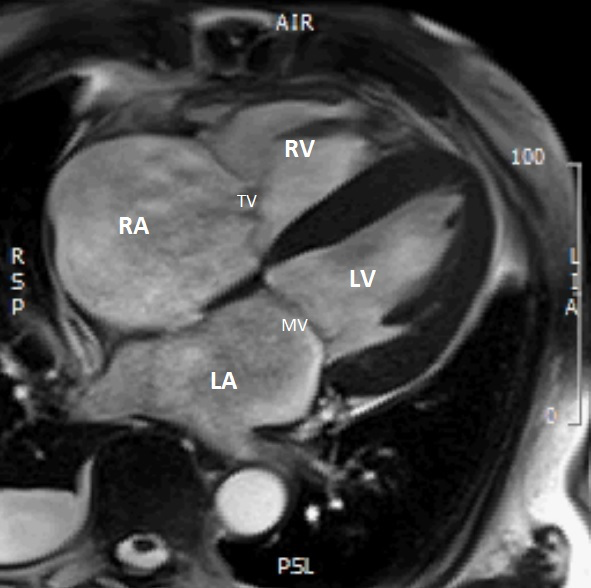

Video 1: MRI cine

MRI beelden – 4 kamer opname. Let op de slechter linkerventrikelfunctie. Let op de verdikte wanden inferolateraal en inferoseptaal

Figuur 2: MRI cine

MRI 4-kamer opname. Let op de uitgebreide afwijkingen in de wand van zowel de linker- als rechterventrikel (witte pijlen). LV = linkerventrikel. RV = rechterventrikel. LA = linkeratrium, RA = rechteratrium, MV = mitralisklep, TV = tricuspidalisklep.